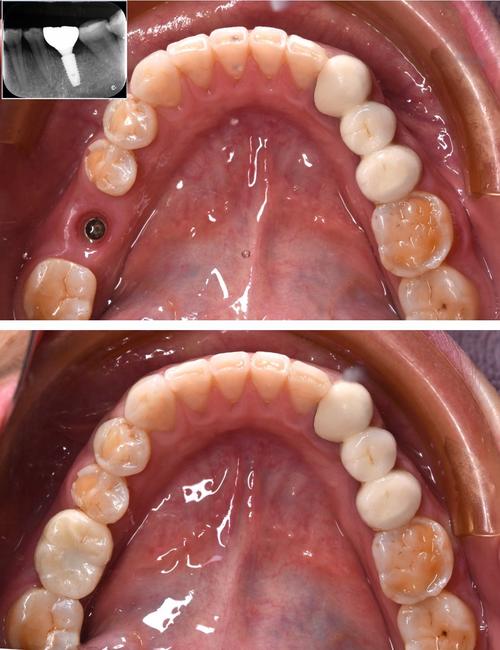

- 能否查看一些成功案例(照片或模型)。